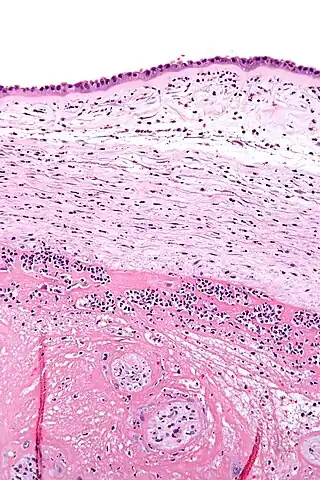

![]() Micrografía mostrando corioamnionitis. Los acúmulos de manchas azules corresponden a células inflamatorias. Tinción hematoxilina-eosina. | ||

La corioamnionitis es una infección del líquido amniótico y las membranas que lo contienen; también se denomina infección intraamniótica, infección ovular o amnionitis y puede ir acompañada de una ruptura prematura de membranas o con el saco amniótico completo.